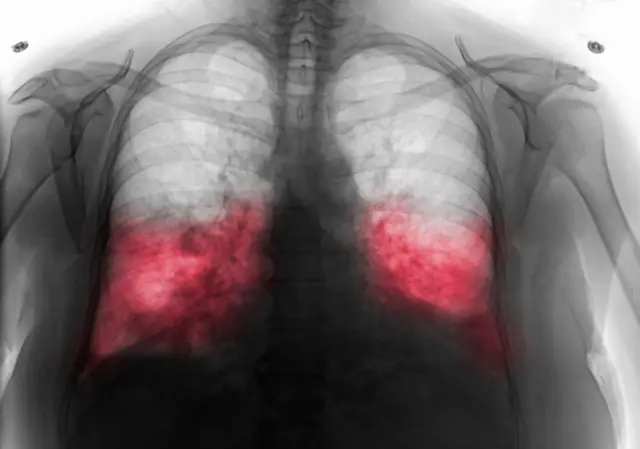

البابا فرنسيس يعاني من الالتهاب الرئوي الثنائي، فما هو هذا المرض؟ وما سبب خطورته؟

أعلن الفاتيكان، إصابة البابا فرنسيس، بالتهاب رئوي في رئتيه، وأن حالته لا تزال معقدة. ويعاني البابا البالغ 88 عاماً من عدوى الجهاز التنفسي، منذ أكثر من أسبوع، وأُدخل إلى مستشفى جيميلي، في روما يوم الجمعة.

وقال الفاتيكان إن الفحص بالأشعة المقطعية، على صدر البابا فرانسيس، كشف عن المراحل المبكرة من الالتهاب الرئوي الثنائي، ما يتطلب المزيد من العلاج الطبي.

الالتهاب الرئوي الثنائي

يُقصد بالالتهاب الرئوي الثنائي، أن العدوى أصابت كلتا الرئتين، وليس رئة واحدة فقط. ومع ذلك، فإن هذا لا يجعل الإصابة أكثر حدة بالضرورة، وفقاً لما يقوله باحثون من جامعة سيدني للتكنولوجيا.

ويؤدي الالتهاب الرئويّ إلى التهاب الأكياس الهوائية، داخل الرئتين. يُمكن أن تمتلئ هذه الأكياس بالسوائل، ما يؤدي إلى ظهور أعراض، مثل السعال المصحوب بالبلغم، أو الصديد (القيح) والحمّى والقشعريرة وآلام الجسم والارتباك وصعوبة التنفس.